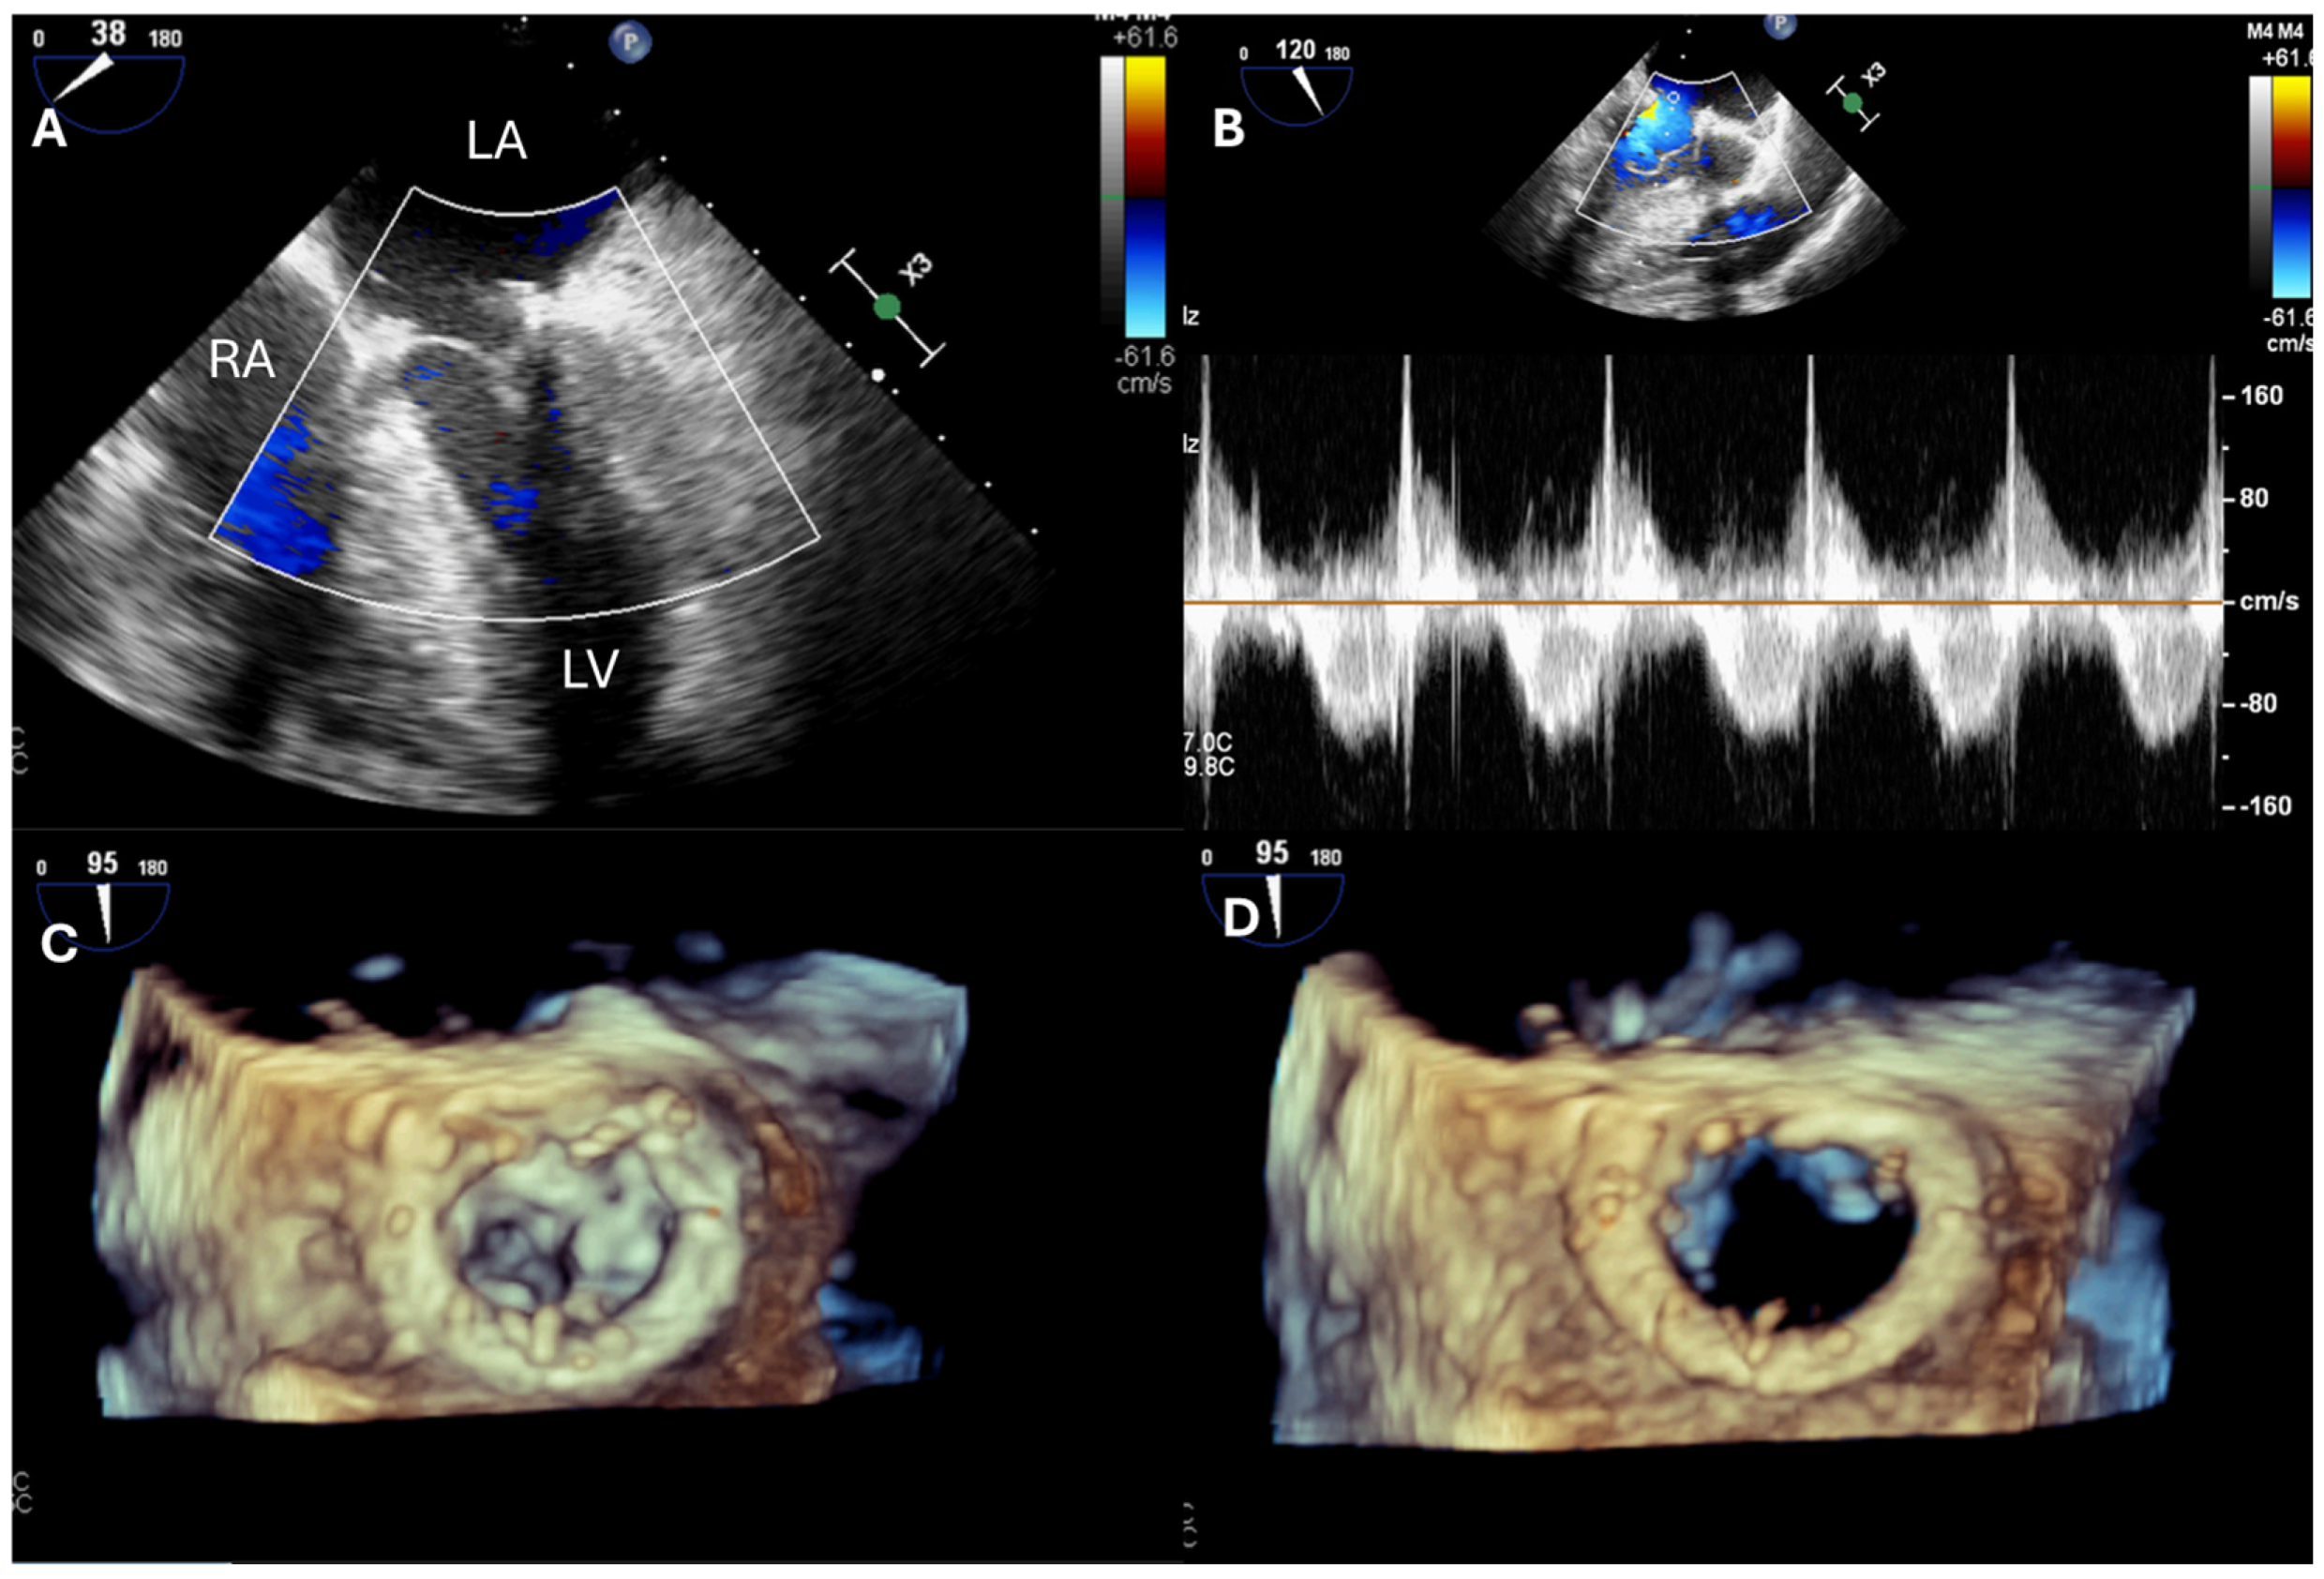

4. Tricuspid Valve Disease

| TV repair | Describe TR mechanism Describe TV anatomy Measure TV annulus | Exclude iatrogenic TV stenosis |